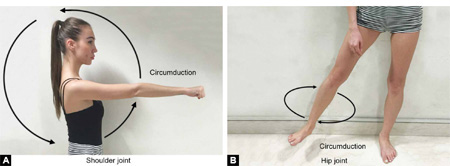

Circumduction (Figs. 1.7A and B): It is a combination of flexion, extension, abduction and adduction. In this movement distal end of a limb makes a conical movement and the apex of the cone is at the proximal end of the limb.